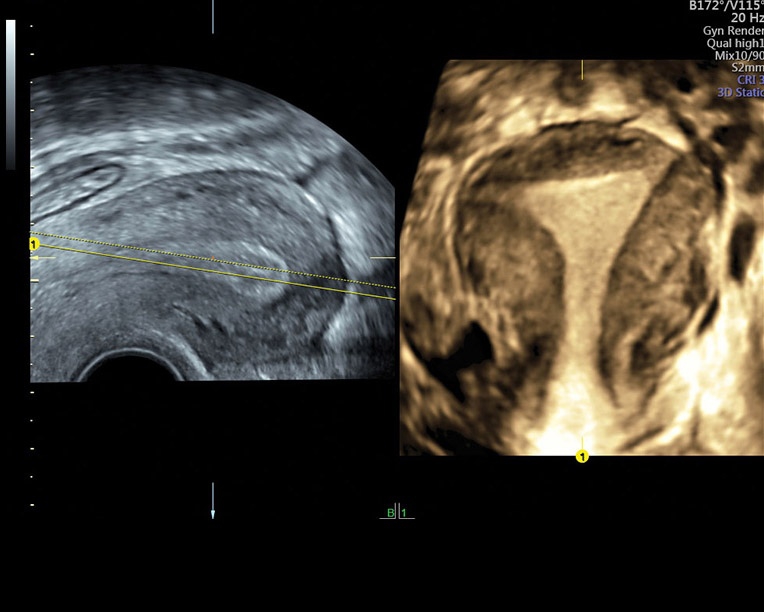

Преимущества аппарата Voluson P8 в области акушерства и гинекологии включают:

• Простота проведения обследований: Аппарат Voluson P8 предоставляет простоту использования при проведении обследований в акушерстве и гинекологии. Независимо от телосложения пациента и плотности кожной ткани, оборудование обеспечивает высокую точность диагнозов.

• Усовершенствованное цветовое доплеровское картирование: Эта функция позволяет получить более детальное изображение сердечно-сосудистой системы и ее функциональных систем. Она выводит обследование на новый уровень, обеспечивая более точную визуализацию и анализ данных.

• Высокая производительность: Аппарат Voluson P8 обладает высокой производительностью и позволяет проводить пост-обработку изображений как во время, так и после проведения обследования. Это обеспечивает более детальный анализ данных и повышает эффективность общей диагностики.

• Высокочувствительные датчики: Аппарат оборудован высокочувствительными датчиками, которые позволяют визуализировать дополнительные анатомические плоскости. Это расширяет возможности диагностики и обеспечивает более точную оценку состояния пациента.

Аппарат Voluson P8 сочетает простоту использования, высокую точность диагнозов и эффективность обследования в области акушерства и гинекологии. Он предоставляет медицинскому персоналу мощный инструмент для более точной диагностики и улучшения обслуживания пациентов.

• Акушерство и гинекология: Voluson P8 обеспечивает высокую точность диагностики беременности, оценку развития плода, обследование матки и яичников, а также другие акушерские и гинекологические исследования.